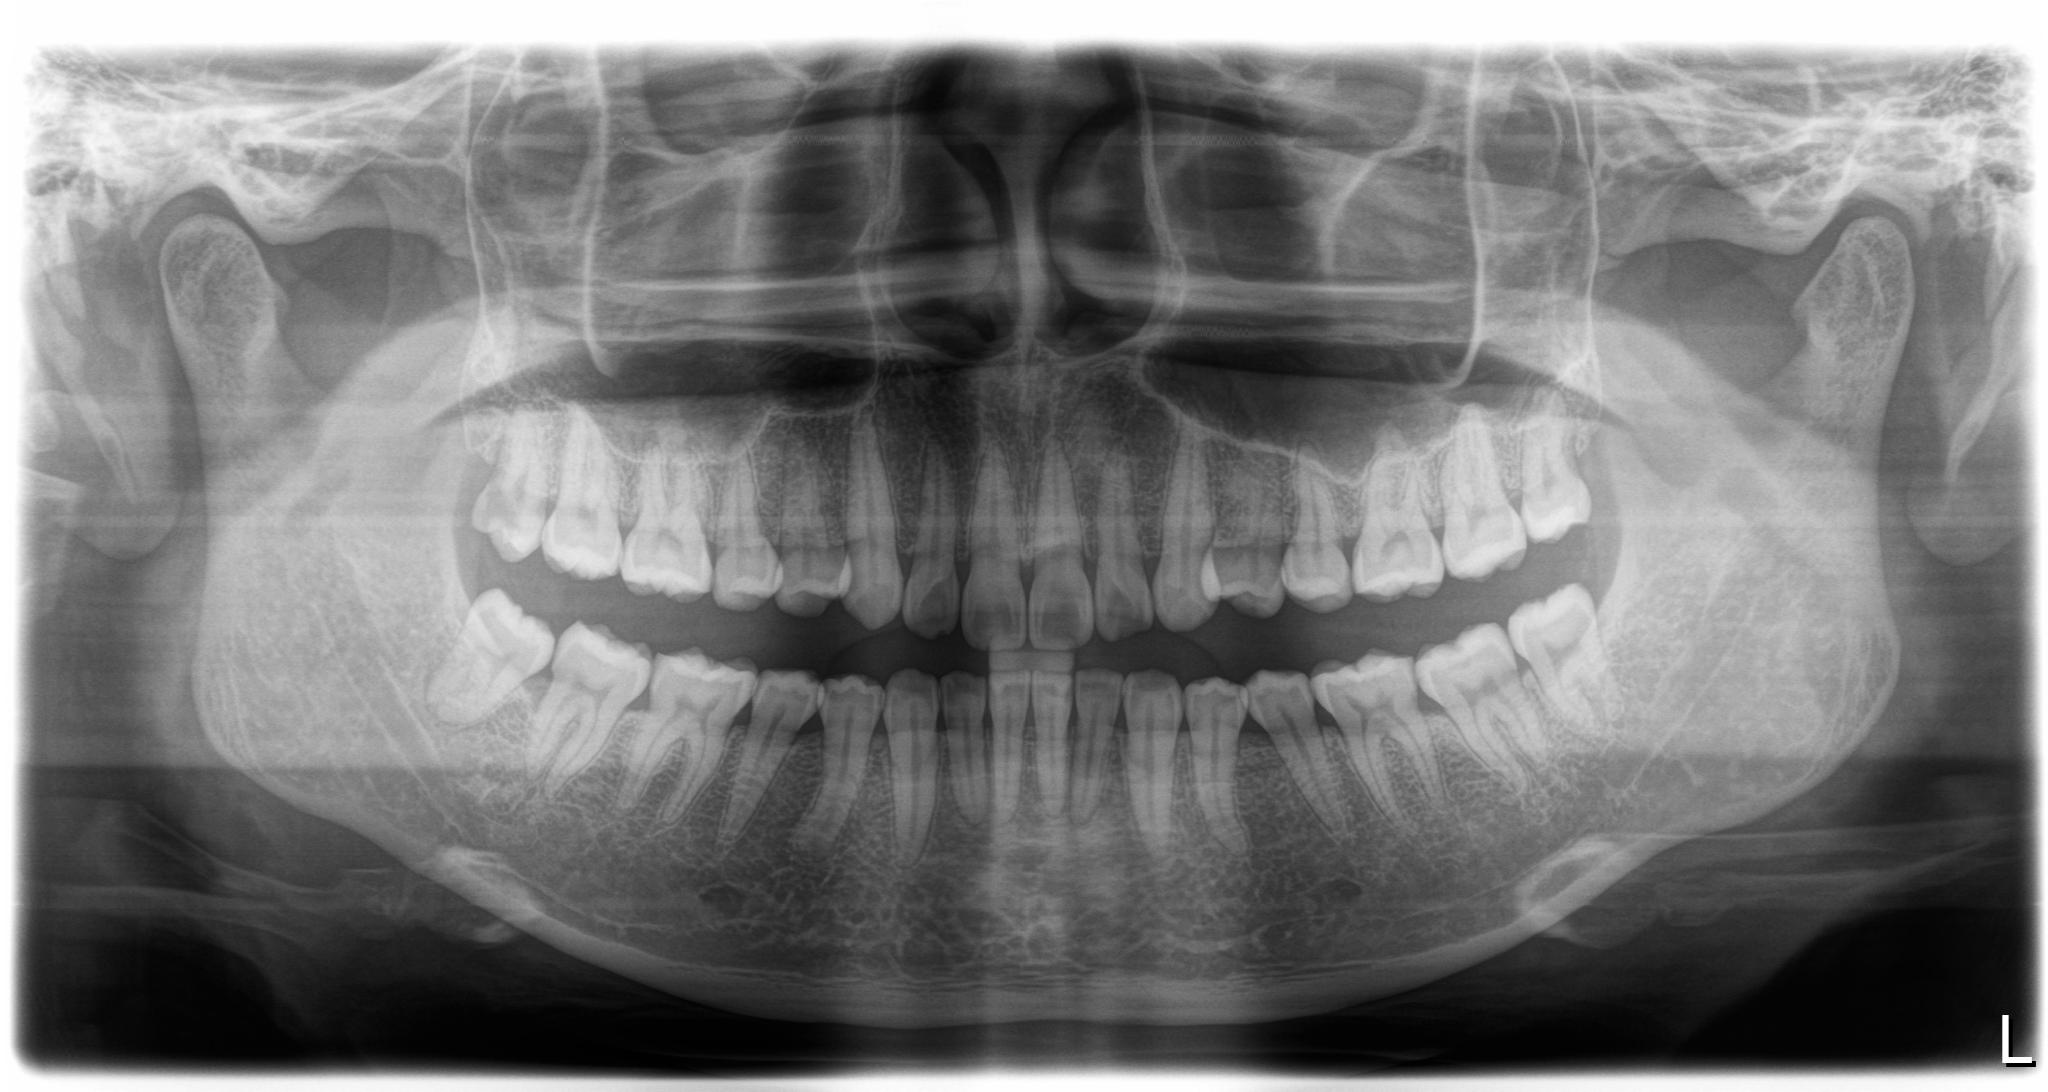

上图示:18岁的刚刚成年的小孩,通过拍片发现牙根发育逐渐完全,智齿逐渐萌出的开始,慢慢随着时间逐渐长出,但是影像显示萌出的空间受限,导致垂直向阻萌,但是上合的智齿萌出的可能性比较大,对于这类的智齿一般上面的智齿后期拔除,下颌的智齿择期拔除。这类情况基本没有造成影响,但对于颌骨发育基本定型了,萌出量的大体基本能掌握,对于后期的影响能有直接的预判了。

上图示:25岁的年轻人,通过片子我们发现下面的智齿都是近中阻生生长,后期会影响到前牙,具体如何可以看前面文章的介绍智齿的危害,对于这类智齿的处理是果断拔除,而对合生长的智齿存在伸长的影响,这类的情况建议择期拔除就ok了。

上图示:33岁的中年人,对于该智齿示完全萌出,空间也是很够的, 但是对于图片的左上角的智齿一篇暗暗的影像,代表已经蛀牙厉害了,这类情况是直接拔除,而对于图片的左下角智齿则是择期拔除,而图片的右侧智齿则是建议维护好口腔卫生就行的。

上图示:38岁的中年人,对于上面的智齿的话一般从长远考虑上面的智齿是拔除的,下面的智齿定期拍片检查,只要不存在影响到邻牙的牙根,可以着情不处理因为经过多年的发展,这类影响的可能性很低或者没有,除非后期牙周不佳,也可以直接果断地拔除智齿。

通过上图的全景片,大体了解不同年龄段对于智齿的生长,如何通过影像去检查,了解它的生长形态,需不需要拔除的处理,大概是什么时候最佳时间段。一般是18-25岁最佳,再往后有些可能已经造成影响,有些可能还在潜伏期中。